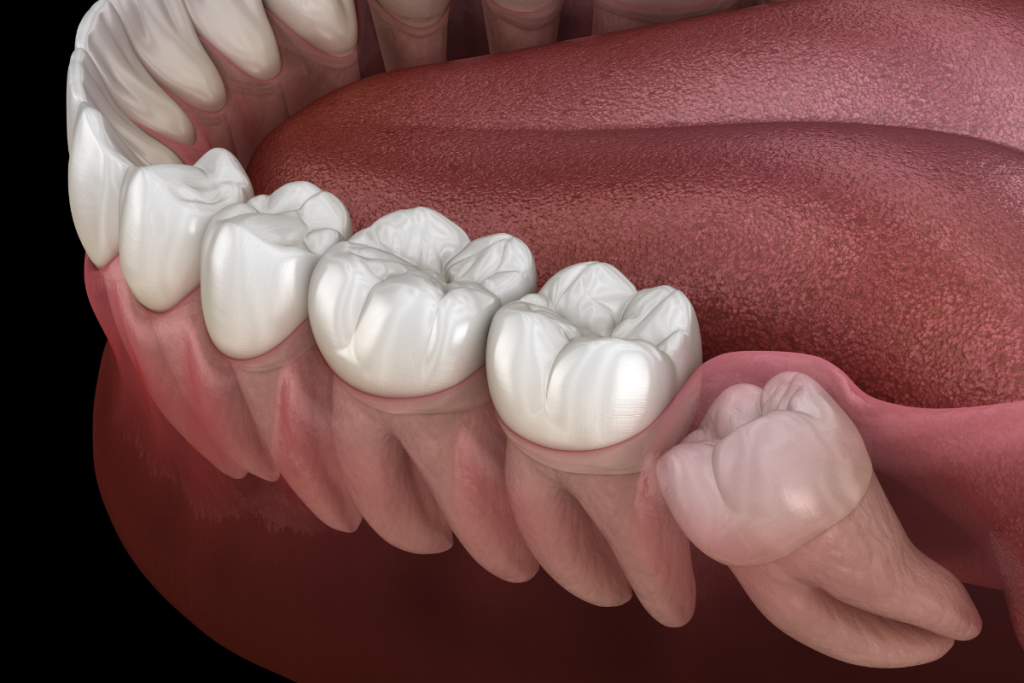

Wisdom tooth removal and other dental surgeries can be performed with minimal pain and discomfort, thanks to advancements in dental anesthesia and sedation techniques.